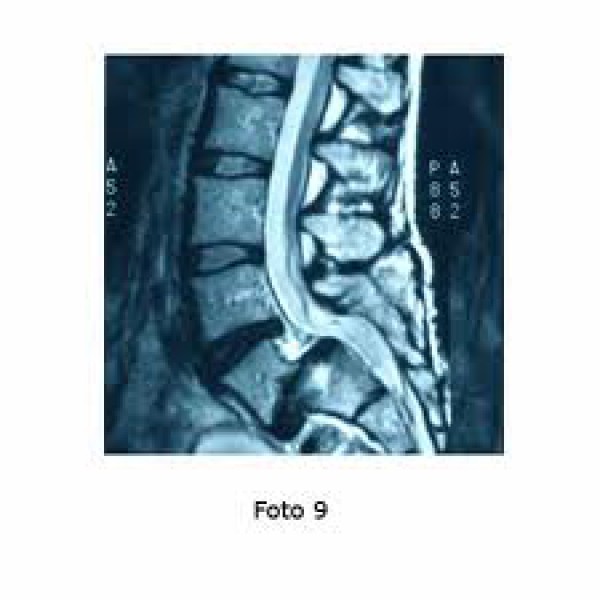

Ressonância magnética lombar: Permite uma boa visão do disco, mostrando com clareza a hérnia de disco e a compressão das estruturas nervosas. Também demonstra alterações iniciais degenerativas do e protusões discais.